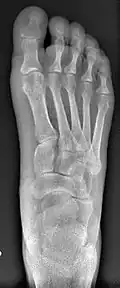

Primus varus deformity

Primus varus deformity is the leaning of the first metatarsal bone away from the second metatarsal and towards the opposite foot (Fig. 1). As it leans over, its head sticks out to form the bunion bump and it also widens the forefoot to cause shoes feeling too tight. Thus when bunion pain becomes unmanageable, surgical correction is to narrow the forefoot by repositioning of the first metatarsal head back to its normal position. This can be done by osteotomy (bone-breaking), soft tissue (non-osteotomy) or fusion techniques.

Syndesmosis procedure addresses specifically the two fundamental problems of metatarsus primus varus deformity that gives rise to the bunion deformity. They are leaning and instability of the first metatarsal bone . Syndesmosis procedure uprights the leaning first metatarsal bone with strong binding sutures between it and the second metatarsal bone (Fig. 2) and then also stabilizes it uniquely by creating a fibrous connecting bridge between these two bones (Fig. 3, 4). First metatarsal bone can be readily realigned because by definition of the metatarsus primus varus deformity its first metatarsal is abnormally loose and mobile.